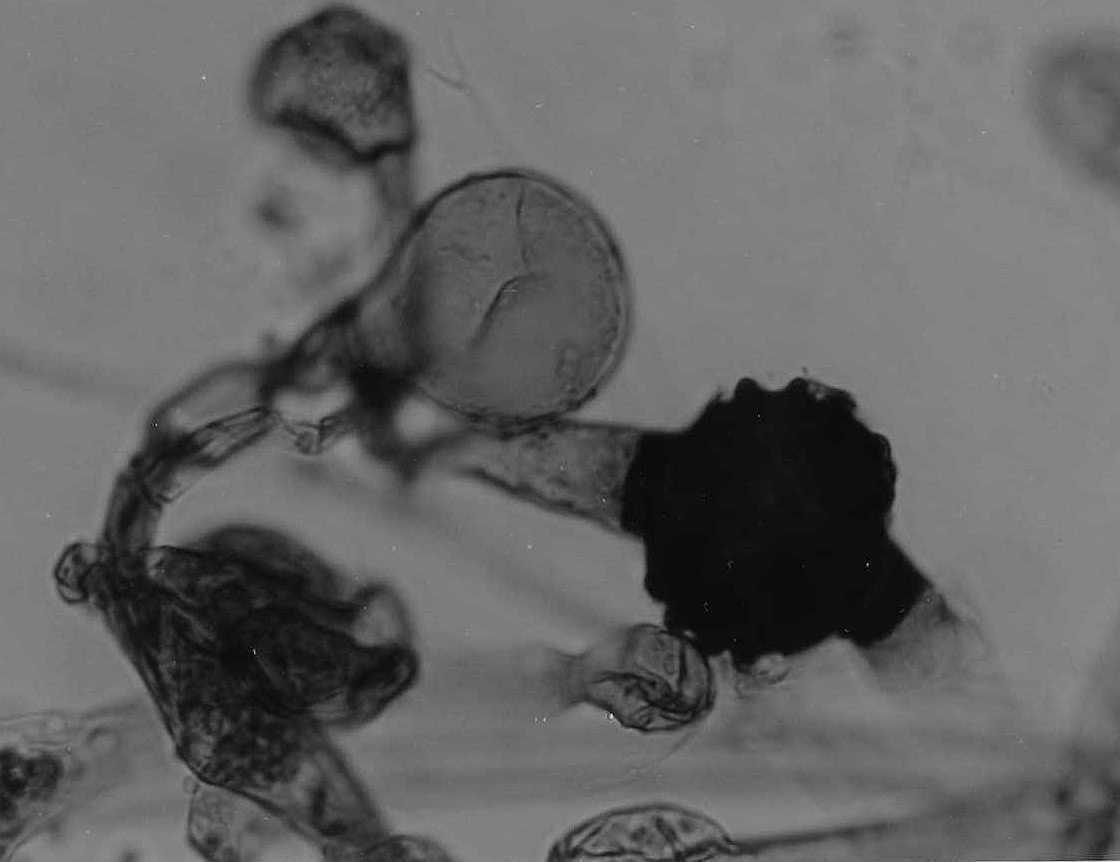

| Species Name: | Rhizomucor pusillus |

| Taxonomy: | FUNGI Mucoromycota, Mucoromycetes, Mucorales, Lichtheimiaceae |

| Substrate: | post mortem lung, male 55 yr with chronic lymphocytic leukemia, treated with fludarabine and prednisone for autoimmune hemolytic anemia |

| Characters: | HUMAN/ ANIMAL PATHOGEN disseminated disease, isolate confirmed by compatibility - // HUMAN/ ANIMAL PATHOGEN disseminated disease, isolate confirmed through compatibility - Weitzman et al., J. Clin. Microbiol. 33:781-783, 1995 (Click for publications citing UAMH 8243) |